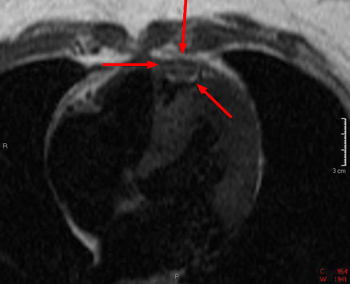

Primary malignancies of the pericardium are rare. The most common is primary pericardial mesothelioma. The pericardium is more commonly a site of metastases from lung, colon, and breast cancer. All metastatic tumors will typically enhance.

These spin echo (left) and gradient echo (right) images show a mass within the pericardium. It is somewhat heterogenous and is not consistent with a benign pericardial cyst. This patient was found to have a pericardial mesothelioma.